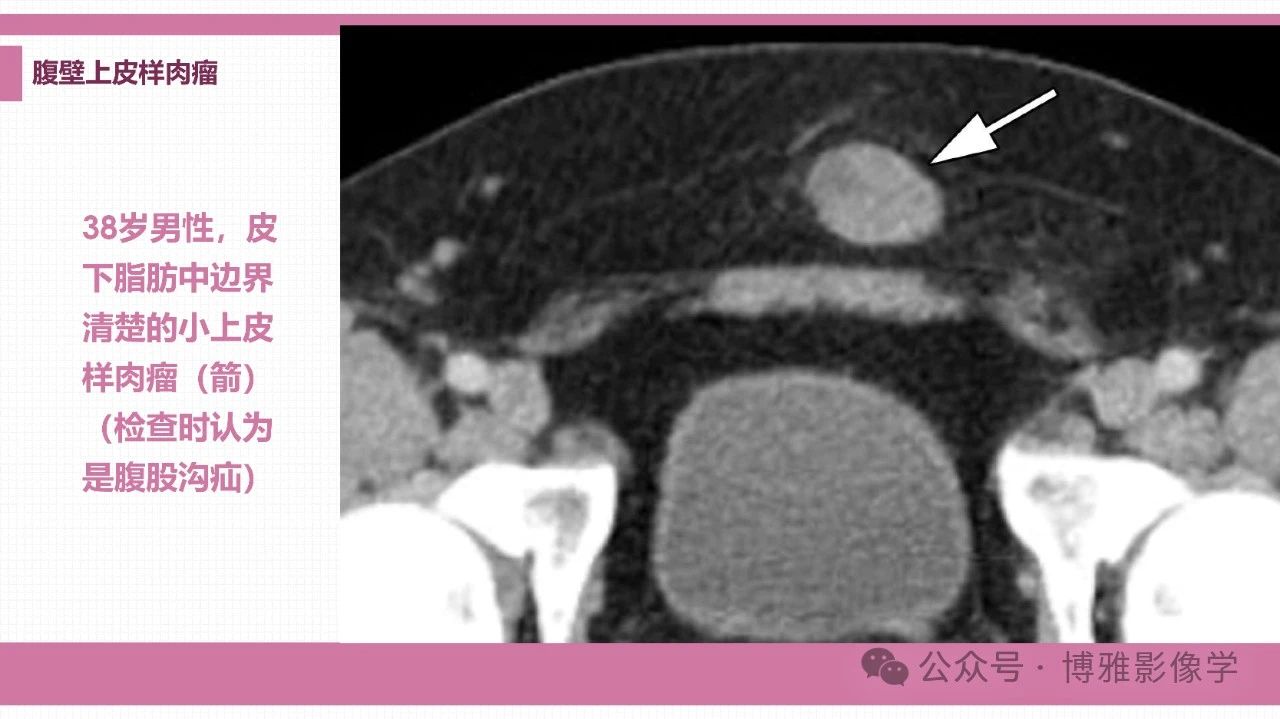

腹壁肿瘤、肿瘤样病变和弥漫性病变的影像学鉴别诊断思路

来源:博雅影像学

李福兴 天津市宝坻区人民医院